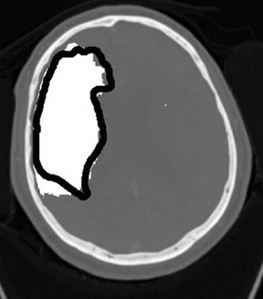

The goal of this study was to examine whether computed tomography angiography source images obtained through three-dimensional convolutional neural networks can help detect ischemic stroke.

Article: 3D convolutional neural networks applied to CT angiography in the detection of acute ischemic stroke